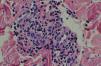

El estudio histopatológico de las lesiones de livedo reveló la existencia de unos vasos profundos con engrosamiento e hiperplasia de su capa media, que se dirigían perpendicularmente hacia la dermis media. La biopsia de los habones de la mama mostró un infiltrado perivascular superficial de linfocitos y neutrófilos con leucocitoclasia sugestiva de urticaria vasculitis (fig. 3). Histopatológicamente la lesión necrótica del pie presentaba una úlcera cutánea cubierta por una escara necrótica y un vaso trombosado recanalizándose en la dermis profunda.

La patogenia del SS es desconocida. El estudio histopatológico de las lesiones cutáneas muestra con frecuencia la oclusión de la luz vascular por la proliferación de la íntima y el cúmulo de células mononucleares, eritrocitos y fibrina2. Se debate si esta oclusión es debida a una disfunción endotelial primaria, a fenómenos trombóticos recurrentes en el contexto de un estado de hipercoagubilidad o a una combinación de ambos mecanismos.